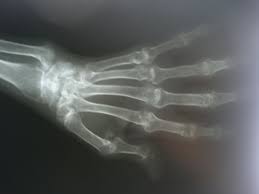

It can affect anyone of any age. </b>small joints of the feet, wrists, and hands are frequently involved by a reduction of osteoporosis; Severe rheumatoid arthritis of the wrist and hand. Rheumatoid arthritis (ra) imaging tests are used to look for signs of ra and to monitor the disease's progression. Ra causes pain, swelling, stiffness, and loss of function in joints.